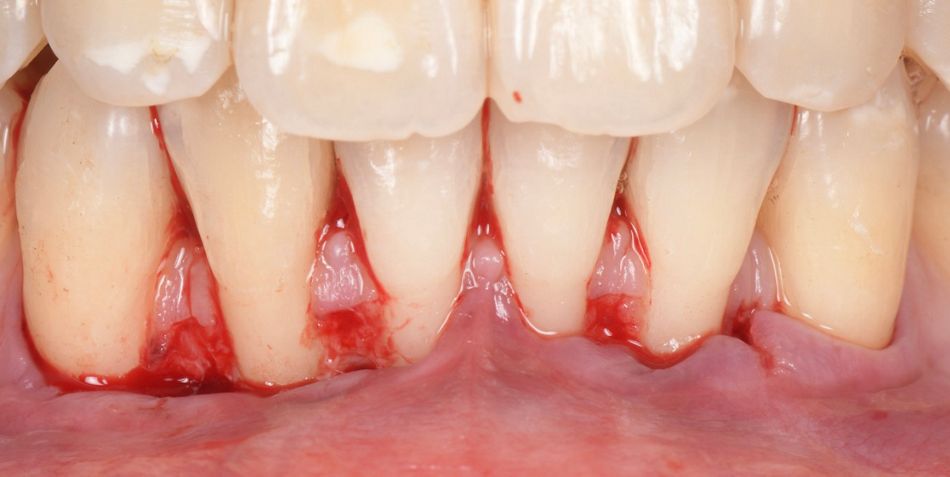

A 35-year-old female, healthy (ASA I), non-smoker, with no medication, came to our practice complaining about gingival recession and pain while brushing her mandibular incisors.

The intraoral examination revealed multiple RT 1 (Cairo 2011) gingival recessions on teeth #33 to #43, along with a thin tissue phenotype, which was associated with a traumatic toothbrushing habit (Fig. 1).